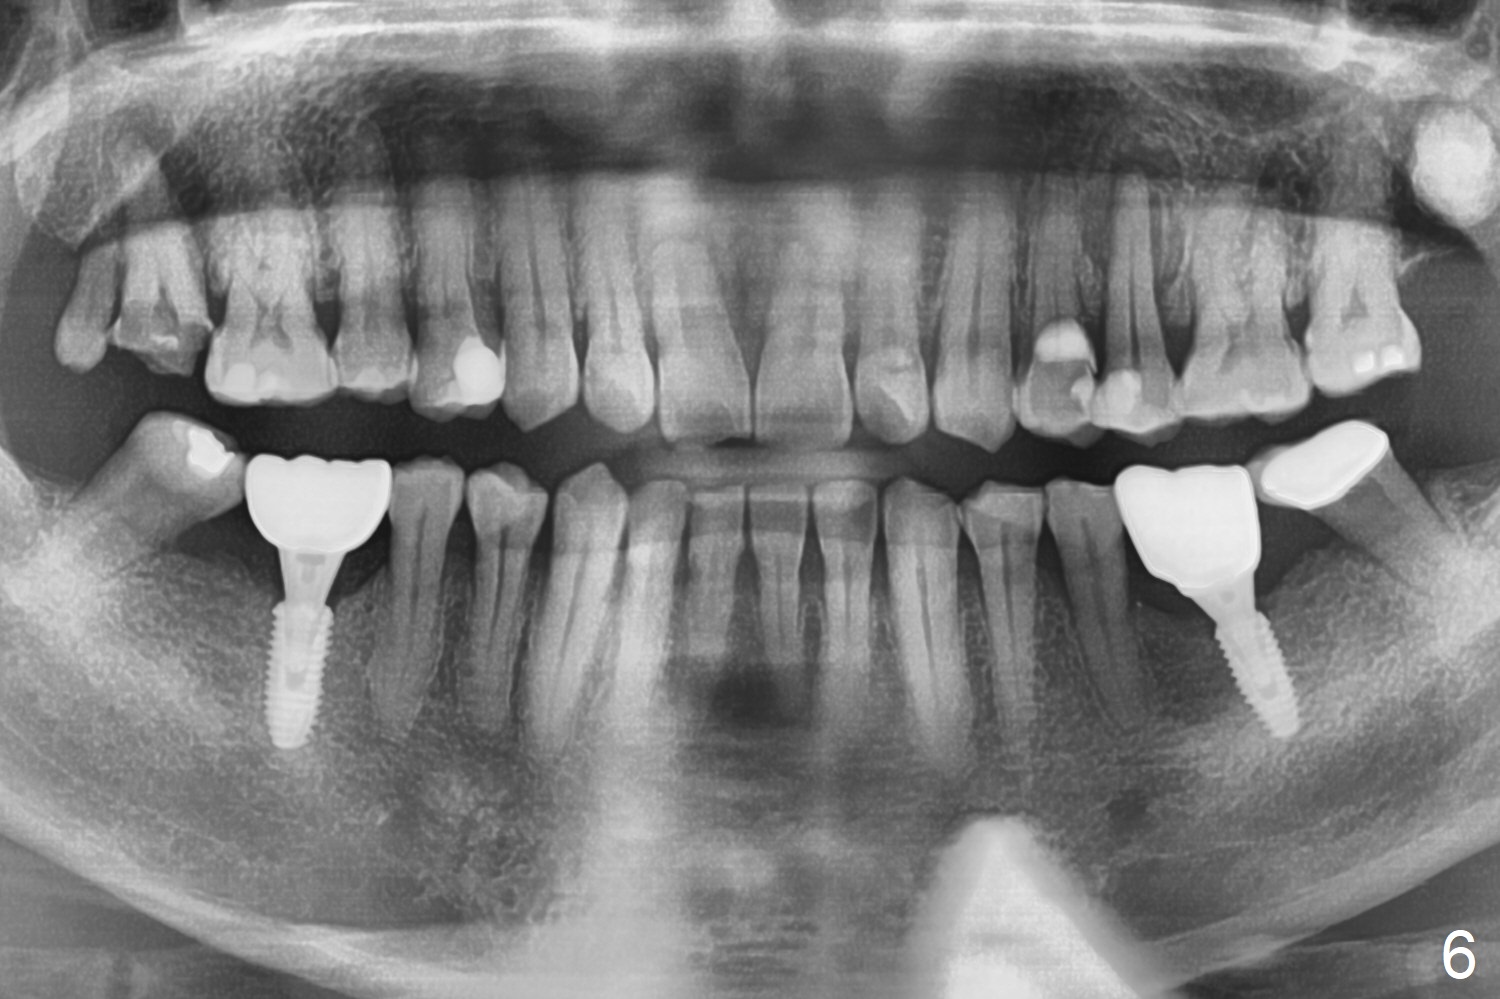

After extraction of the distal residual root at #19 (Fig.1), osteotomy is initiated in the mesial (M) aspect of the distal socket (Fig.2). Magic Split proves dense bone. When a 4.5x10 mm dummy implant is placed with stability, there is an apical space (Fig.3 <); the dummy abutment is 5.7x5.5(2). With the final implant (4.5x10 mm, Fig.4) being placed deeper to close the apical space, the cuff of the final abutment increases by 1 mm. Autogenous bone is used to pack around the implant distobuccally (*). Although the implant seems to be placed significantly apical to the lingual crest (^), it is at the buccal crest. There seems to be no bone loss 3 months postop; impression is taken (Fig.5). The crown/abutment at #30 is retightened 22 days post cementation (5 months postop), probably related to unilateral mastication. In fact, #30 is the only functioning molar on the right side (with unfavorable crown/implant ratio (long cuff 4 mm, vs. 3 mm at #19); #2 severely decayed); the crown at #19 is cemented at the same appointment (Fig.6). The crowns/abutments at #19 and 30 are loose 7 months later. When the crown/abutment at #30 is loose 2nd time 1 year 7 months post cementation, the screw at #19 fractures (Fig.7 taken post retightening). The tooth #2 needs a crown. The patient cannot use the anterior teeth, since the teeth #8 and 9 have root fracture. Can extraction and bone graft increase bone height? The abutment remains incompletely seated 9 months post screw replacement. It should be fixed soon. Return to Lower Molar Immediate Implant, Prevent Molar Periimplantitis (Protocols, Table), Armaments Screw Xin Wei, DDS, PhD, MS 1st edition 12/22/2017, last revision 02/24/2021